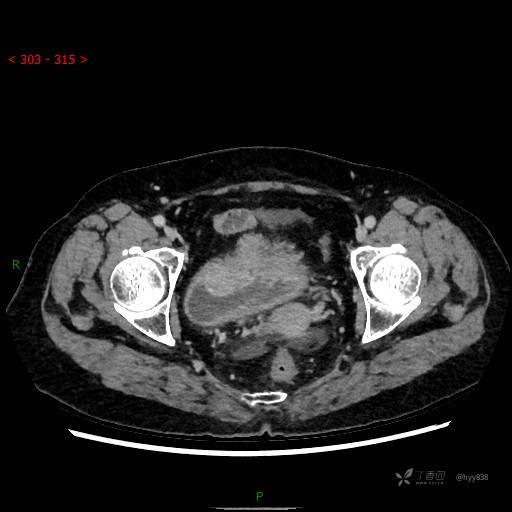

膀胱少见肿瘤,欢迎挑战---结果公布~

华夏览雄 达人已点赞患者性别:女

患者年龄:73岁

主诉:肉眼血尿3周

简要病史:患者诉3周前无明显诱因开始出现肉眼血尿,发作时尿液呈鲜红色,为全程血尿,无明显血凝块;伴小腹胀痛,无尿频、尿急、尿痛;无寒战、发热;无恶心、呕吐,就诊于当地医院行输液治疗后,出现不规则血凝块,进一步完善相关检查提示膀胱占位,活检提示膀胱炎性改变,现患者为进一步治疗,遂来我院,门诊以“膀胱肿物”为主诉入院。 起病以来,患者精神、饮食、睡眠稍差,大便如常,小便如上述,近期体力、重无明显变化

辅助检查:CT

临床诊断:膀胱肿瘤

膀胱CT平扫(2022.10.20)

增强(2022.11.1)